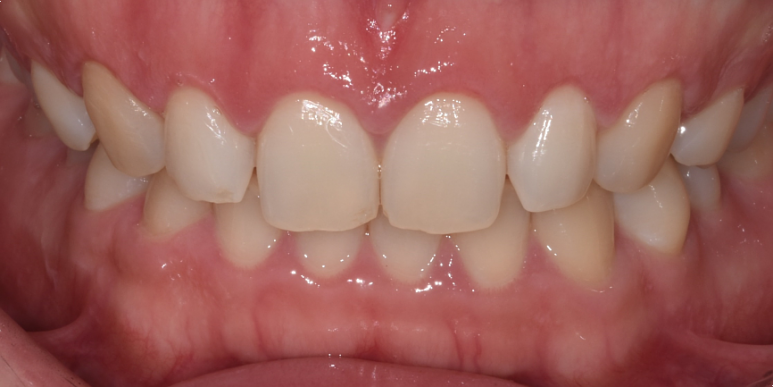

상기 환자분 전체적으로 잇몸라인이 평평하고, 치아가 네모나게 보이는 것이 고민이 되어 잇몸성형을 받기 위해 내원해 주셨습니다.

24세 여성

(전) 2022-06-11, (후) 2022-06-25

레이저를 이용해서 전체적으로 잇몸라인을 동그랗게 다듬어드리고 높이도 양측 균일하게 맞춰드렸습니다.

전후 사진 비교해 보시면 이전보다 치아 형태가 더 예쁘고 시원한 느낌이 드는 것을 확인하실 수 있는데요.

실제 웃거나 말씀하실 때 잇몸이 많이 보이는 것도 고민이셨는데, 이 부분도 개선되어 환자분도 많이 흡족해하셨습니다. ^^

레이저를 이용한 잇몸성형 시술시간은 국소마취 시간을 포함해서 약 30분 정도이며,

레이저로 섬세하게 시술해 드리고 있어 통증과 출혈을 최소화하고 있지만, 개인에 따라 당일 약간의 출혈과 통증, 붓기 등이 있을 수 있고요.

회복되기까지 약 2~3일간은 붉은 기운과 쓰라인 느낌이 있을 수 있습니다.